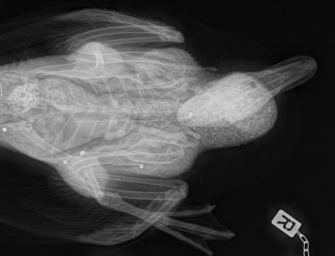

In der vergangenen Woche kommt es auf der Himmelsleiter bei Aachen zu einem Zwischenfall. Ein Tier, allem Anschein nach handelt..